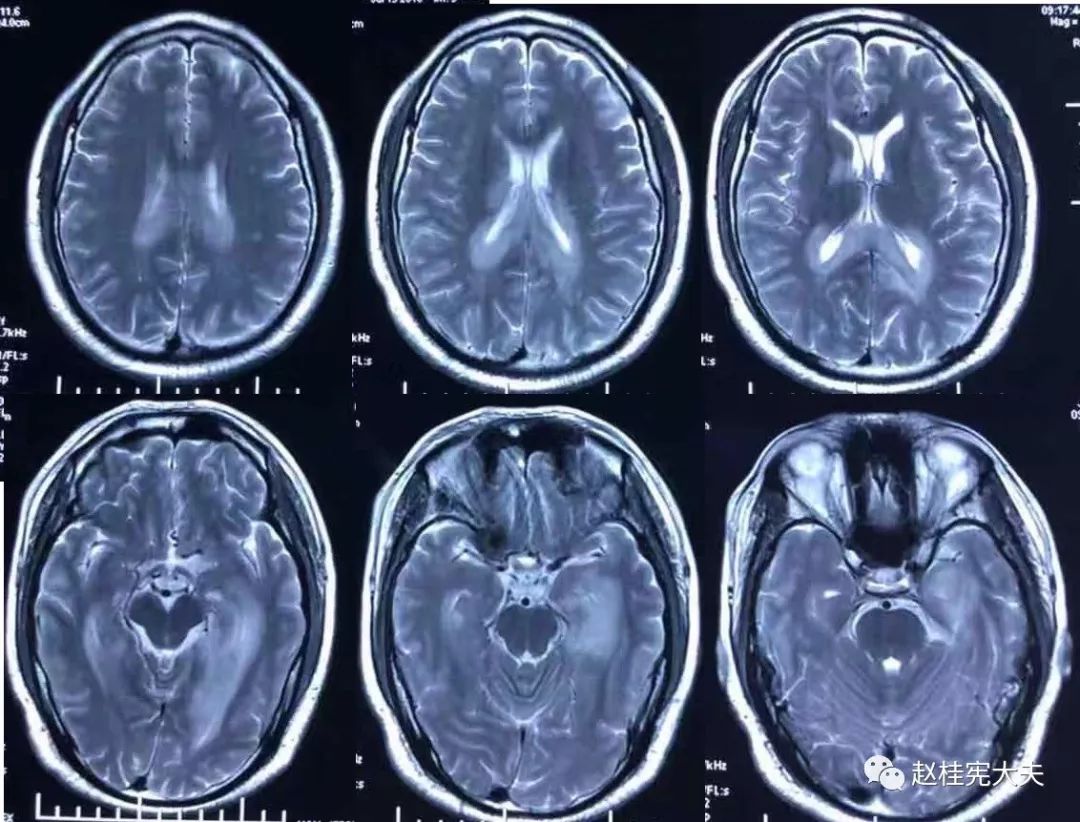

2018.7.6头颅MRI:胼胝体、穹隆及双侧脑室旁、基底节区、右侧延髓、桥臂异常信号,脱髓鞘病变考虑。头颅MRS:左枕叶病变区MRS显示:NAA下降,Cho升高,Cho/NAA=3.86,并见倒置乳酸峰。

2018.7.10磁共振增强:脑室周边病灶轻度强化。

7.20复查头颅MRI平扫:胼胝体、穹隆及双侧脑室旁、基底节区、右侧延髓、桥臂广泛信号异常,对照前片(7.10)范围明显缩小。

2018.10复查头颅MRI:胼胝体压部、左侧部分枕颞叶、侧脑室枕角旁、中脑脱髓鞘病变,视神经脊髓炎谱系病?结合对照前片(7.4)病变范围有所缩小。

我看到患者时的思考:当了解了患者前期诊疗经过后,在看到患者磁共振片子时,我的第一反应就是淋巴瘤。尽管患者激素治疗后症状有好转,病灶在磁共振上看起来也是有好转,但淋巴瘤也会出现这样的表现。

我对满脑室边的病灶的体会是:遇到这样的病例,首先要考虑感染、肿瘤(如室管膜瘤、生殖细胞瘤、淋巴瘤或转移瘤脑室播散等等),炎症要放到后面去考虑,脱髓鞘的诊断要打个大大大大的?。炎症中,血管炎不像,自免脑也不是很支持,尽管边缘系统似乎也有受累,但患者边缘叶脑炎的精神、行为异常、癫痫等症状很少,而且磁共振上看去除了边缘系统,整个脑室系统都有受累,这个和常见自免脑不符。视神经脊髓炎谱系病?尽管病灶在水通道蛋白富集区,但这样的视神经脊髓炎(视神经和脊髓均未受累,近脑室边的异常信号)至少罕见,即使诊断,也应该是排除其它的疾病后才可能考虑。

患者住院期间还请眼科会诊,除双眼玻璃体轻度浑浊,视力、视野、OCT均未见明显异常,未建议行玻切明确诊断。患者入院后嗜睡症状有加中,但一直未诉头痛,仅是头昏,静滴甘露醇症状减轻不明显。复查头颅磁共振平扫+增强:病灶范围较前明显扩大。轻度强化。